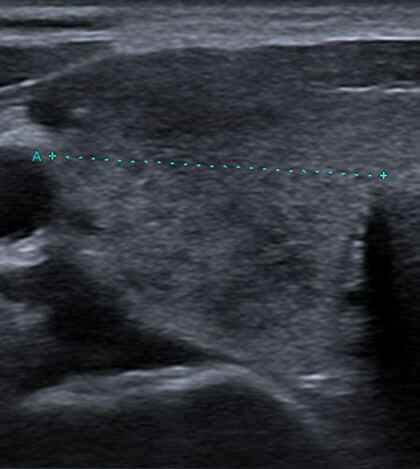

治療前

患部が黒っぽく映る「低エコー像」が特徴的です。また、触診で非常に硬いしこりのように触れることがあります(「石のように硬い」と表現されることもあります)。